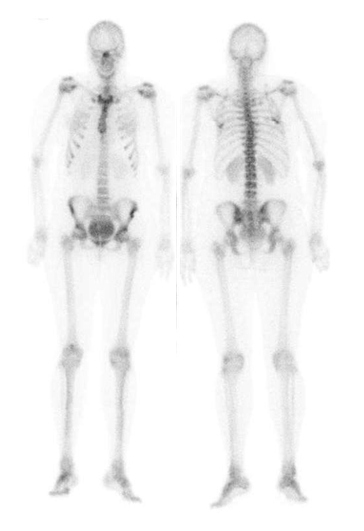

El diagnóstico inicial es de probable sepsis sin foco evidente, por lo cual se comienza tratamiento con antibióticos por vía endovenosa durante 5 días. Sin embargo, dada la usencia de mejoría clínica, los datos de laboratorio y al agregar una cuadriparesia proximal con mayor compromiso de miembros inferiores, se plantea síndrome de Guillain-Barré, por lo cual se suspenden los antibióticos y se inicia tratamiento con inmunoglobulinas. En la evolución aparece dolor lumbar lo que lleva a pensar en una espóndilodiscitis, solicitándose un centellograma óseo (fig. 1).

El hallazgo centellogáfico es compatible con el diagnóstico de rabdomiolisis, presentando hipercaptación renal probablemente secundaria a la sobrecarga de mioglobina. El diagnóstico se confirma con determinación de CPK total > 20.000 u/L (VN 20 -167). Dada la insuficiencia renal aguda, la presencia de mioglobinuria, las cifras de CPK y la imagenología de rabdomiolisis, se plantea síndrome neuroléptico maligno (SNM) por interacción medicamentosa. Se realiza tratamiento en base a diuréticos, hidratación y corrección de las alteraciones iónicas, sumada al retiro de neurolépticos; con buena respuesta al mismo, es dada de alta 12 días después con una CPK total de 199 u/l.

Un año más tarde la paciente se encuentra clínicamente bien y el médico tratante solicita un centellograma óseo de control que resulta prácticamente normal (fig. 2).

Es importante reconocer las diversas causas que pueden producir captación extraósea de 99mTc-MDP, una de las cuales es la rabdomiolisis, que se manifiesta como una intensa incorporación del radiofármaco al músculo esquelético. Otras condiciones que se pueden acompañar de captación muscular son la miodermatomiositis, la amiloidosis, la miositis por VIH y la miositis osificante(8,9). En el presente caso el diagnóstico de rabdomiolisis fue sugerido por el centellograma óseo, ya que hasta ese momento no se había planteado tal posibilidad, permitiendo así instituir las medidas terapéuticas adecuadas.